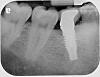

Fig 3. Fractured abutment screw.

Figure 3

Fig 4. Bending of the abutment prongs as a result of

motion caused by screw fracture.